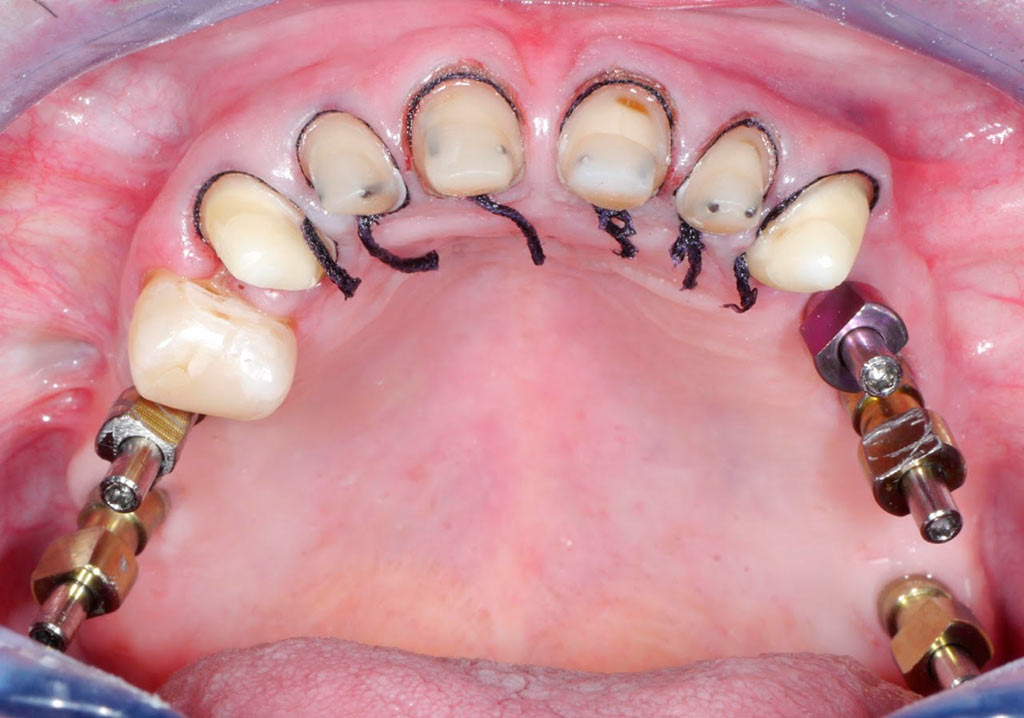

Rehabilitacion de paciente con destrucción dental